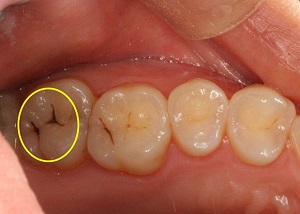

- 음주, 흡연, 군것질 섭취 증가하면 충치균 활동도 왕성해져, 음식물 섭취 후 양치질 꼭 해야 해 - 6개월에 한 번씩 정기 검진해야, 작은 충치라도 초기에 발견한다면 힘든 치료 예방할 수 있어 취업 준비생 하군(29)은 얼마 전부터 치통에 시달렸다. 충치가 있다는 건 알고 있었지만 취업 준비생에게 치과 치료는 사치라 생각하고 차일피일 미뤘다. 시간이 지나면 나아지겠지 생각하고 진통제를 복용하며 통증을 참았지만 시간이 지날수록 통증이 심해져 귀, 볼까지 아프고 잠도 못 잘 정도였던 것. 병원을 찾은 하 씨는 ‘급성치수염’이라는 진단을 받고 신경치료에 들어갔다. 치수염이란 충치로 인해 치아 내 신경조직(치수)에 감염이 일어나 염증이 생기면서 극심한 통증이 유발되는 질환이다. 치아의 중심부에 있는 신경이나 혈관이 지나가는 곳을 ‘치수’라고 한다. 충치가 심하게 진행돼 치수와 가까워지면 치아 속 신경에 염증을 일으킬 수 있다. 즉, 혈관이 확장되고 충혈돼 혈액량이 증가되면서 압력이 올라가 극심한 통증을 느끼게 되는 것이다. 치수염은 충치 외에도 치아에 금이 가거나 심한 충격이 가해졌다면 생길 수 있는데 자연치유가 되지 않아 치료가 반드시 필요한 질환이다. 특히 급성 치수염의 경우 수면 시 극심한 통증을 느낄 수 있는데 누워 있을 때 머리 쪽으로 혈액이 많이 몰리게 되면서 치아 내부의 혈관이 확장되고 압력 또한 더욱 높아지기 때문이다. 인간이 느끼는 통증 중 정도가 심한 3대 통증이 있는데 산통, 요로결석과 함께 급성 치수염의 고통이 꼽힐 정도다. 만성의 경우는 염증이 아주 천천히 진행돼 통증을 느끼는 정도가 미약하기 때문에 그냥 지나치기가 쉽다. 치아가 어둡게 변하거나, 치아 뿌리 아래에 고름이 생겨서 음식을 씹을 때 통증을 느끼고 나서야 염증을 알게 되는 경우가 많은 것. 일산 사과나무치과병원 김현영 부원장은 “치수염은 그냥 방치해두면 치아뿌리 및 주위 치주조직으로 염증이 진행돼 치아와 잇몸을 손상시킬 수 있고, 심한 경우는 치아를 발치해야 하는 경우도 있어 조기 치료가 중요하다”며 “급성 치수염의 경우 심한 통증 때문에 환자들이 자발적으로 치과를 찾아와 치료를 하지만 만성 치수염은 증상이 미약해 그냥 지나치는 경우가 많은데 치아 뿌리 주위 조직까지 염증이 번졌는데도 아무런 증세를 자각하지 못하는 경우도 있기 때문에 적기에 신경 치료를 하고 크라운을 씌우는 치료를 받으면 대부분 치료에 성공할 수 있다”고 말했다. 치수염이 생기는 가장 큰 원인은 충치를 그냥 방치해 두기 때문이다. 특히 스트레스가 심한 직장인이나 수험생에게서 치통이 많이 나타날 수 있는데 잦은 음주와 흡연, 군것질 섭취가 증가하게 되고 구강 건강관리에 소홀하게 되면서 충치균의 활동도 왕성해질 수 있어 음식물 섭취 후에는 반드시 양치질을 해줘야 한다. 찬물을 마시거나 찬 음식에 이가 시린 경우에도 치과를 방문해 검진을 받는 것이 좋다. 김원장은 “치수염을 예방하기 위해서는 6개월에 한 번씩 주기적인 스케일링을 받고 정기 검진을 통해 작은 충치도 초기에 발견할 수 있도록 해야 하고 필요하다면 X-ray 촬영을 통해 확인하는 것이 좋다”며 “하지만 무엇보다 중요한 것은 올바른 양치 습관을 갖는 것이다. 양치질을 할 때는 치아 겉면만 닦는 것이 아니라 치실과 치간칫솔을 이용해 치아 사이 면도 꼼꼼히 닦아줘야 한다”고 덧붙였다. 【도움말 = 일산 사과나무치과병원 김현영 부원장】 [김현지 기자] munandpil@nate.com | |||||||||